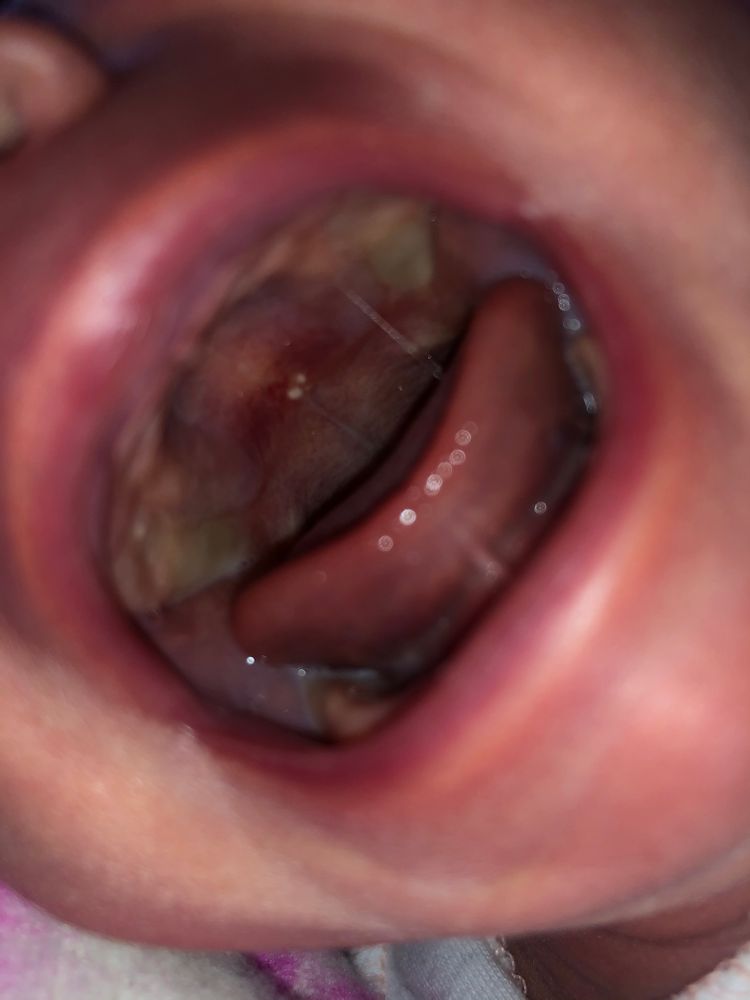

Красное нёбо у новорожденного

Страхи, переживания и немножечко нытьяВсем привет! Увидела у дочки вот такое покраснение. Может кто знает что это?